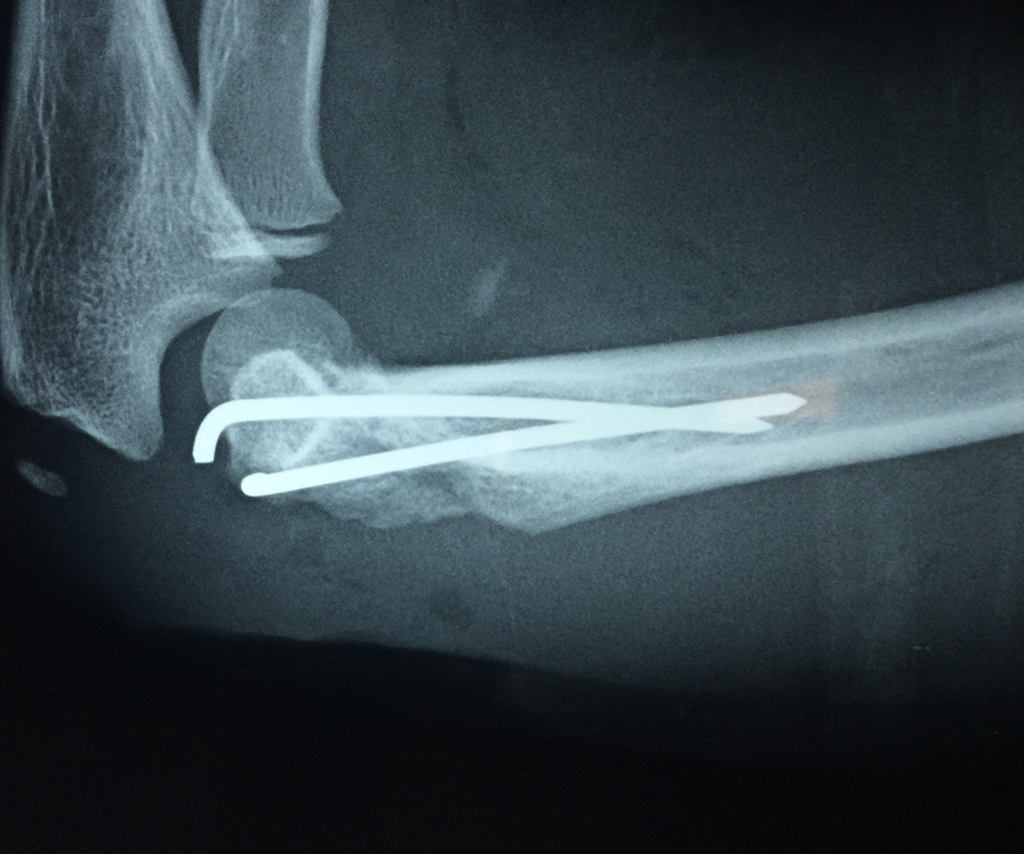

En anatomía humana, la articulación del codo es la que une el brazo con el antebrazo, conectando la parte distal del hueso húmero con los extremos proximales de los huesos cúbito y radio.

La articulación principal que constituye el codo se denomina humero radio-cubital y puede dividirse en dos partes bien diferenciadas, la articulación humero-radial y la humero-cubital.

Por otra parte el cúbito y el radio forman también una articulación entre si en las proximidades del codo, la cual se denomina articulación radio-cubital proximal.